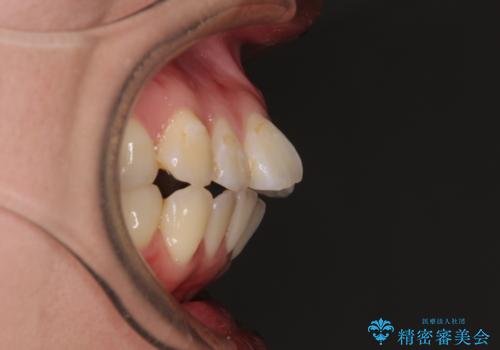

術中や仕上がりに特に大きなトラブルはなく、スムーズに治療を終えることができました。

【モニター】処置歯の多い歯列 インビザラインでデコボコを整える

- 上下前歯のデコボコを気にして来院された患者様です。